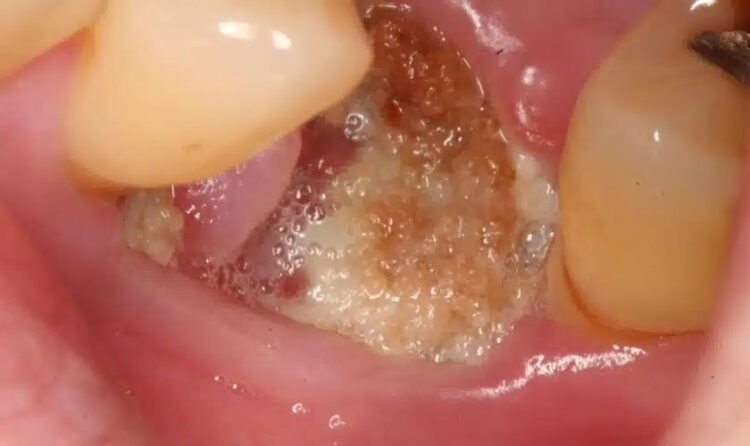

An infected tooth, often called a dental abscess, occurs when bacteria invade the pulp – the innermost part of your tooth containing nerves and blood vessels. This infection can be incredibly painful and, if left untreated, can spread to other parts of your body. Symptoms typically include severe toothache, sensitivity to hot and cold, swelling in the gum or face, and sometimes even a fever.

Recognizing these signs early is crucial for effective treatment. Prompt action can often prevent the infection from worsening and save your tooth.